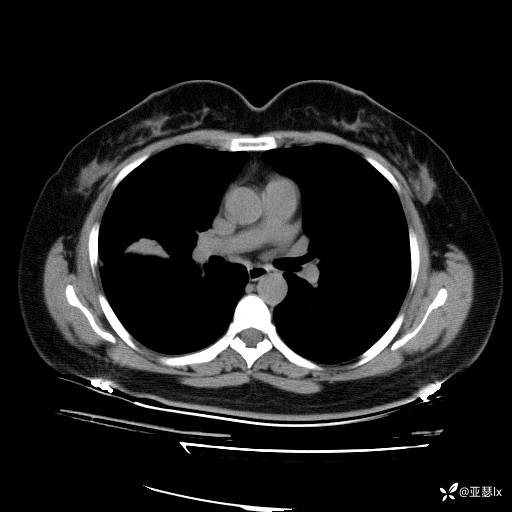

影像学:

初步诊断:社区获得性肺炎

诊断依据:1.社区发病;2.病史及体征:咳嗽、发热等急性感染表现;查体:右肺可闻及湿罗音,触觉语颤增强;3.实验室检查:感染指标明显升高;影像学:右肺实变影。